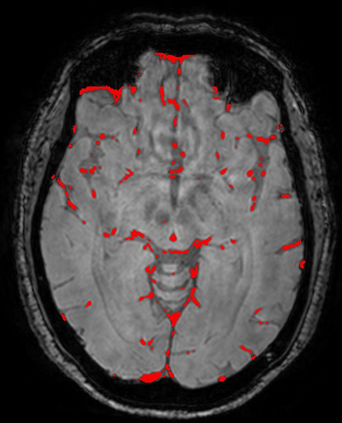

The use of deep learning techniques for 3D brain vessel image segmentation has not been as widespread as for the segmentation of other organs and tissues. This can be explained by two factors. First, deep learning techniques tend to show poor performances at the segmentation of relatively small objects compared to the size of the full image. Second, due to the complexity of vascular trees and the small size of vessels, it is challenging to obtain the amount of annotated training data typically needed by deep learning methods. To address these problems, we propose a novel annotation-efficient deep learning vessel segmentation framework. The framework avoids pixel-wise annotations, only requiring patch-level labels to discriminate between vessel and non-vessel 2D patches in the training set, in a setup similar to the CAPTCHAs used to differentiate humans from bots in web applications. The user-provided annotations are used for two tasks: 1) to automatically generate pixel-wise labels for vessels and background in each patch, which are used to train a segmentation network, and 2) to train a classifier network. The classifier network allows to generate additional weak patch labels, further reducing the annotation burden, and it acts as a noise filter for poor quality images. We use this framework for the segmentation of the cerebrovascular tree in Time-of-Flight angiography (TOF) and Susceptibility-Weighted Images (SWI). The results show that the framework achieves state-of-the-art accuracy, while reducing the annotation time by up to 80% with respect to learning-based segmentation methods using pixel-wise labels for training